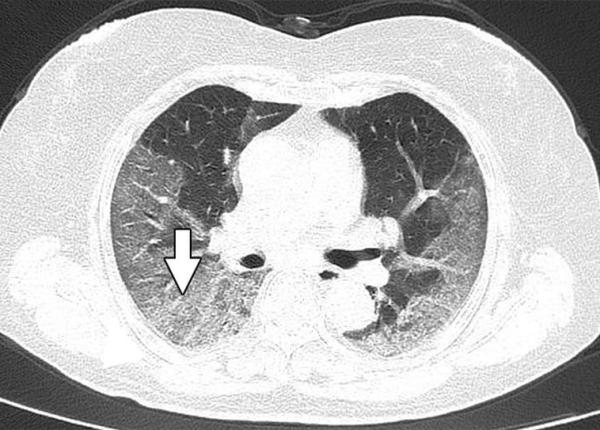

Pneumonia dată de coronavirus, cum afectează plămânii. Constatări făcute la CT